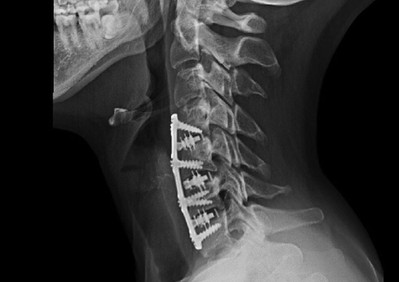

Anterior Cervical Plate System

El sistema de placas cervicales Prodorth está diseñado para satisfacer las expectativas clínicas de la cirugía cervical anterior y ofrece una amplia gama de tamaños de placas y tornillos.

- Placas predobladas de bajo perfil (2,0 mm).

- El sistema de placa cervical de Prodorth consta de placas cervicales, casquillos de cierre, tornillos óseos y los instrumentos necesarios para implantar este sistema específico. Todos los componentes del implante están hechos de una aleación de titanio Ti6Al4V-ELI (Grado 23) (ASTM F136 / ISO 5832-3).